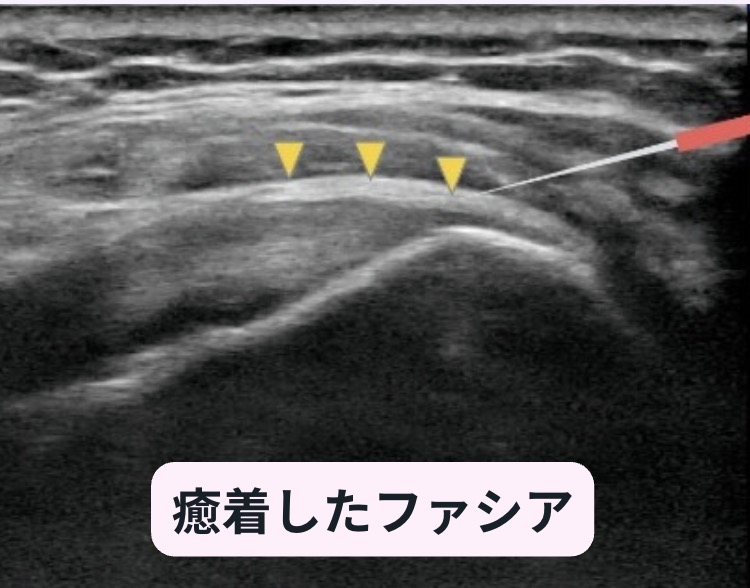

慢性の痛みの多くは、筋肉そのものではなく、筋肉などを包む「ファシア」の癒着が原因です。

当院のはり治療では、この癒着部をエコーで確認し、そこへピンポイントで鍼を届かせることができます。